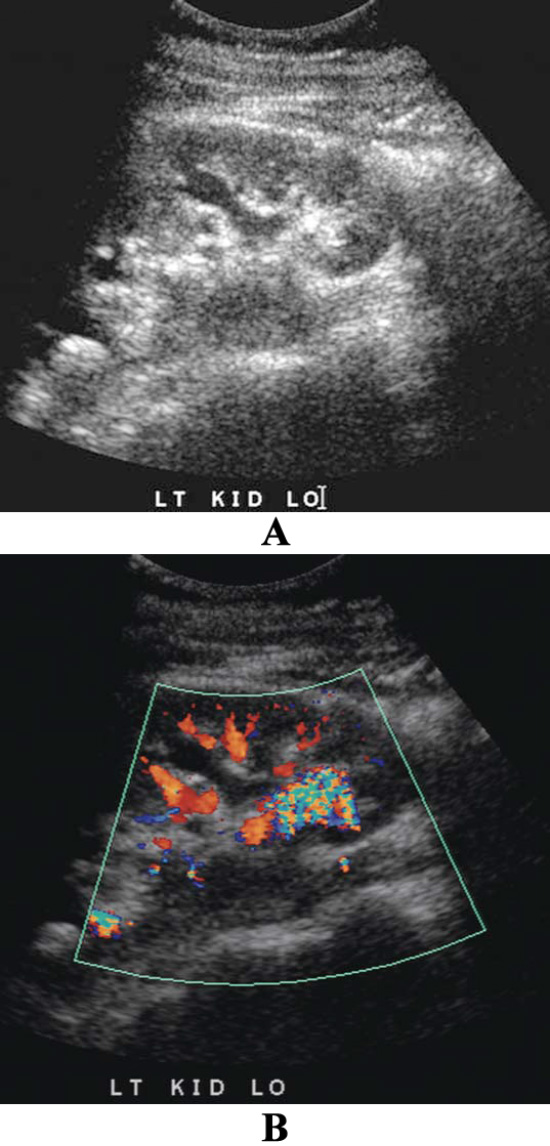

Артефакт мерцания наблюдается за сильно отражающими поверхностями (например, камни в мочевыделительной системе или в почечной паренхиме). Артефакт характеризуется быстро сменяющимися допплеровскими сигналами с характерным спектром и зашумлением. Визуализация артефакта мерцания в большей степени зависит от настроек аппарата ультразвукового исследования и, как правило, возникает при узком диапазоне и внутреннем источнике шума аппарата УЗИ – так называемое фазовое дрожание (часовое дрожание) (фото 1 и 2).

УЗИ почек: артефакт мерцания при камнях в почках

Фото 2. УЗИ почек: артефакт мерцания при камнях в почках. А – черно-белое изображение демонстрирует слабый эхогенный очаг в нижнем полюсе почки и еще один очаг – в верхнем полюсе почки. Эти очаги сложно отличить от синуса. Тени отсутствуют. В – цветное допплеровское исследование демонстрирует интенсивное мерцание (разноцветные пиксели) позади камней, также наблюдается нормальный цвет потока почечных сосудов. Камни в почках трудно диагностировать без обнаружения мерцания